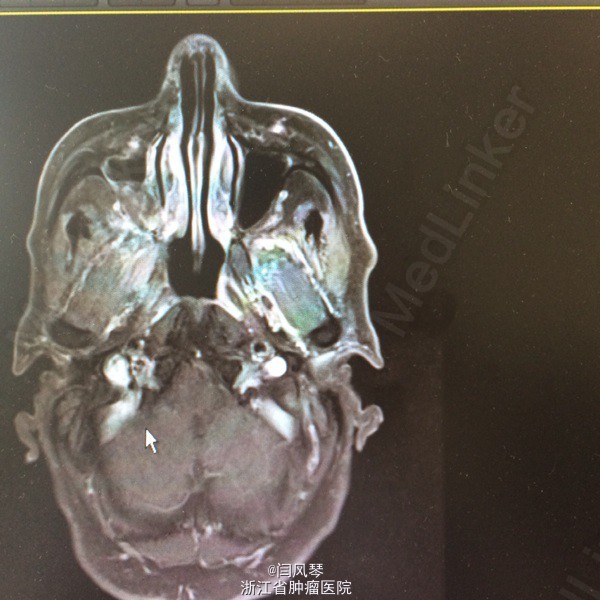

患者男,58岁,鼻咽癌放疗近2年,因鼻咽部复发于2015.6.12-2015.8.25于当地医院行TP方案化疗4周期,现化疗后1月余,诉右耳听力下降,右侧口角周围皮肤麻木感,为进一步诊治就诊于我院,门诊拟“鼻咽恶性肿瘤复发”收治。

一般可,生命体征平稳,鼻咽右侧壁及顶壁见新生物,双颈部未及明显肿大淋巴结。

诊断:鼻咽恶性肿瘤复发。治疗:复发灶局部放疗

讨论:患者鼻咽部放疗后复发,行4周期化疗后,肿瘤残留较明显,有局部放疗指征,但患者首程放疗后近两年,时间较短,再程放疗易引起鼻咽部溃疡大出血、放射性脑病、放射性神经损伤灯较严重的并发症,需积极预防及治疗